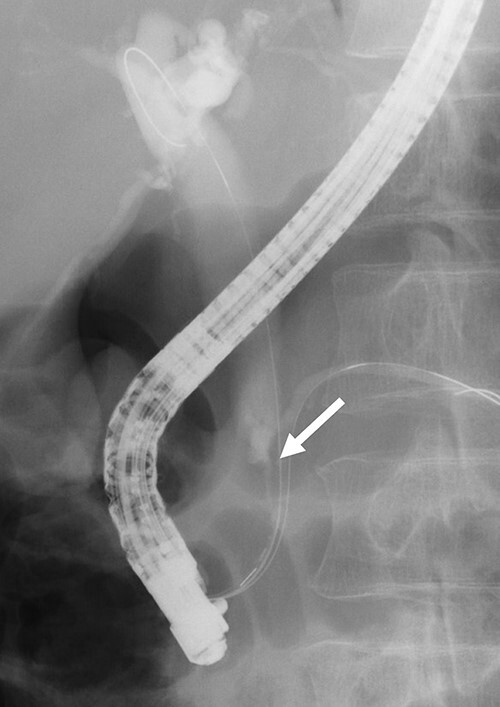

Contrast-enhanced computed tomography (CT) revealed wall thickening and stricture of the distal common bile duct (CBD) (Fig. 1). Dilation of both the intrahepatic bile ducts and the common hepatic duct was also observed (Fig. 2). No lymph node or distant metastases were observed. Endoscopic retrograde cholangiopancreatography revealed irregular stenosis in the distal CBD (Fig. 3). Thereafter, biliary drainage and brush cytology were performed, and an adenocarcinoma was detected.